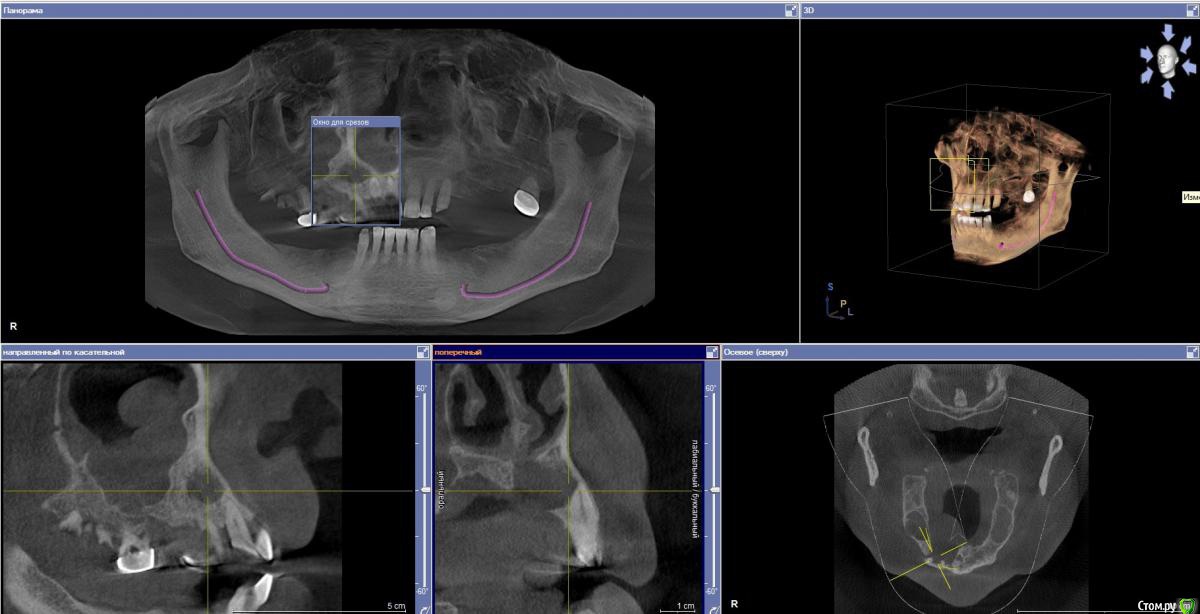

Doctormet Опубликовано 30 октября, 2015 Поделиться Опубликовано 30 октября, 2015 Доктора, приветствую! Нужна помощь в одном клиническом случае!Пациент обратился с целью протезирования. Жалоб на день осмотра не было. Замечал увеличивающееся образование в области неба в течение года. Осмотр: отмечается стираемость зубов передней группы на н\ч и в\ч примерно на 1 мм. Зубы 1.1, 1.2, 1.3 интактные, перкуссия безболезненная. В области твердого неба справа плотное безболезненное образование.Рентгенограмма: Разрежение включает верхушки корней 1.2, 1.3, 1.1, отсутствует латеральная стенка резцового канала, дно полости носа от 1.1 до 1.3 и небная стенка альвеолярного отростка от 1.1 до 1.5. Отмечается двустороннее затемнение верхнечелюстных пазух.Пациент заядлый курильщик. Травм в анамнезе не отмечает.В планах сдача анализов на гепатит, ВИЧ, сифилис, исключение сахарного диабета.Что можно предположить в данном случае? Связано ли данное образование с перегрузкой передних зубов, ЛОР патологией, либо же это киста носонебного канала или опухолевое образование?Снимки прилагаю. Спасибо! Ссылка на комментарий